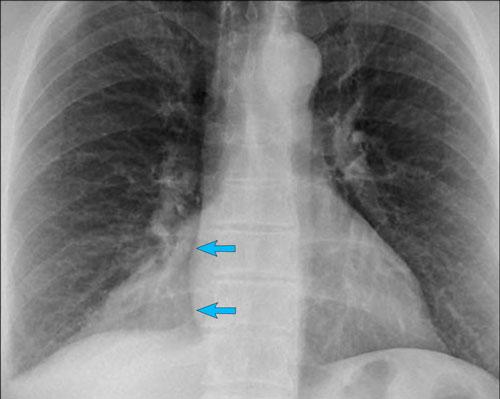

Một mặt tiếp giáp trung thất–phổi quan trọng cần đánh giá là ngách tĩnh mạch đơn–thực quản (mũi tên vàng).

Ngách tĩnh mạch đơn–thực quản

Lệch đường tĩnh mạch đơn–thực quản có thể do:

- Thoát vị khe thực quản

- Bệnh lý thực quản

- Giãn nhĩ trái

- Hạch to dưới carina

- Nang phế quản

Trên phim X-quang ngực tư thế PA, có thể thấy đường tĩnh mạch đơn–thực quản bị lệch sang bên.

Nguyên nhân là do thoát vị khe thực quản.

Mũi tên chỉ vào thuốc cản quang barium trong túi thoát vị khe thực quản.